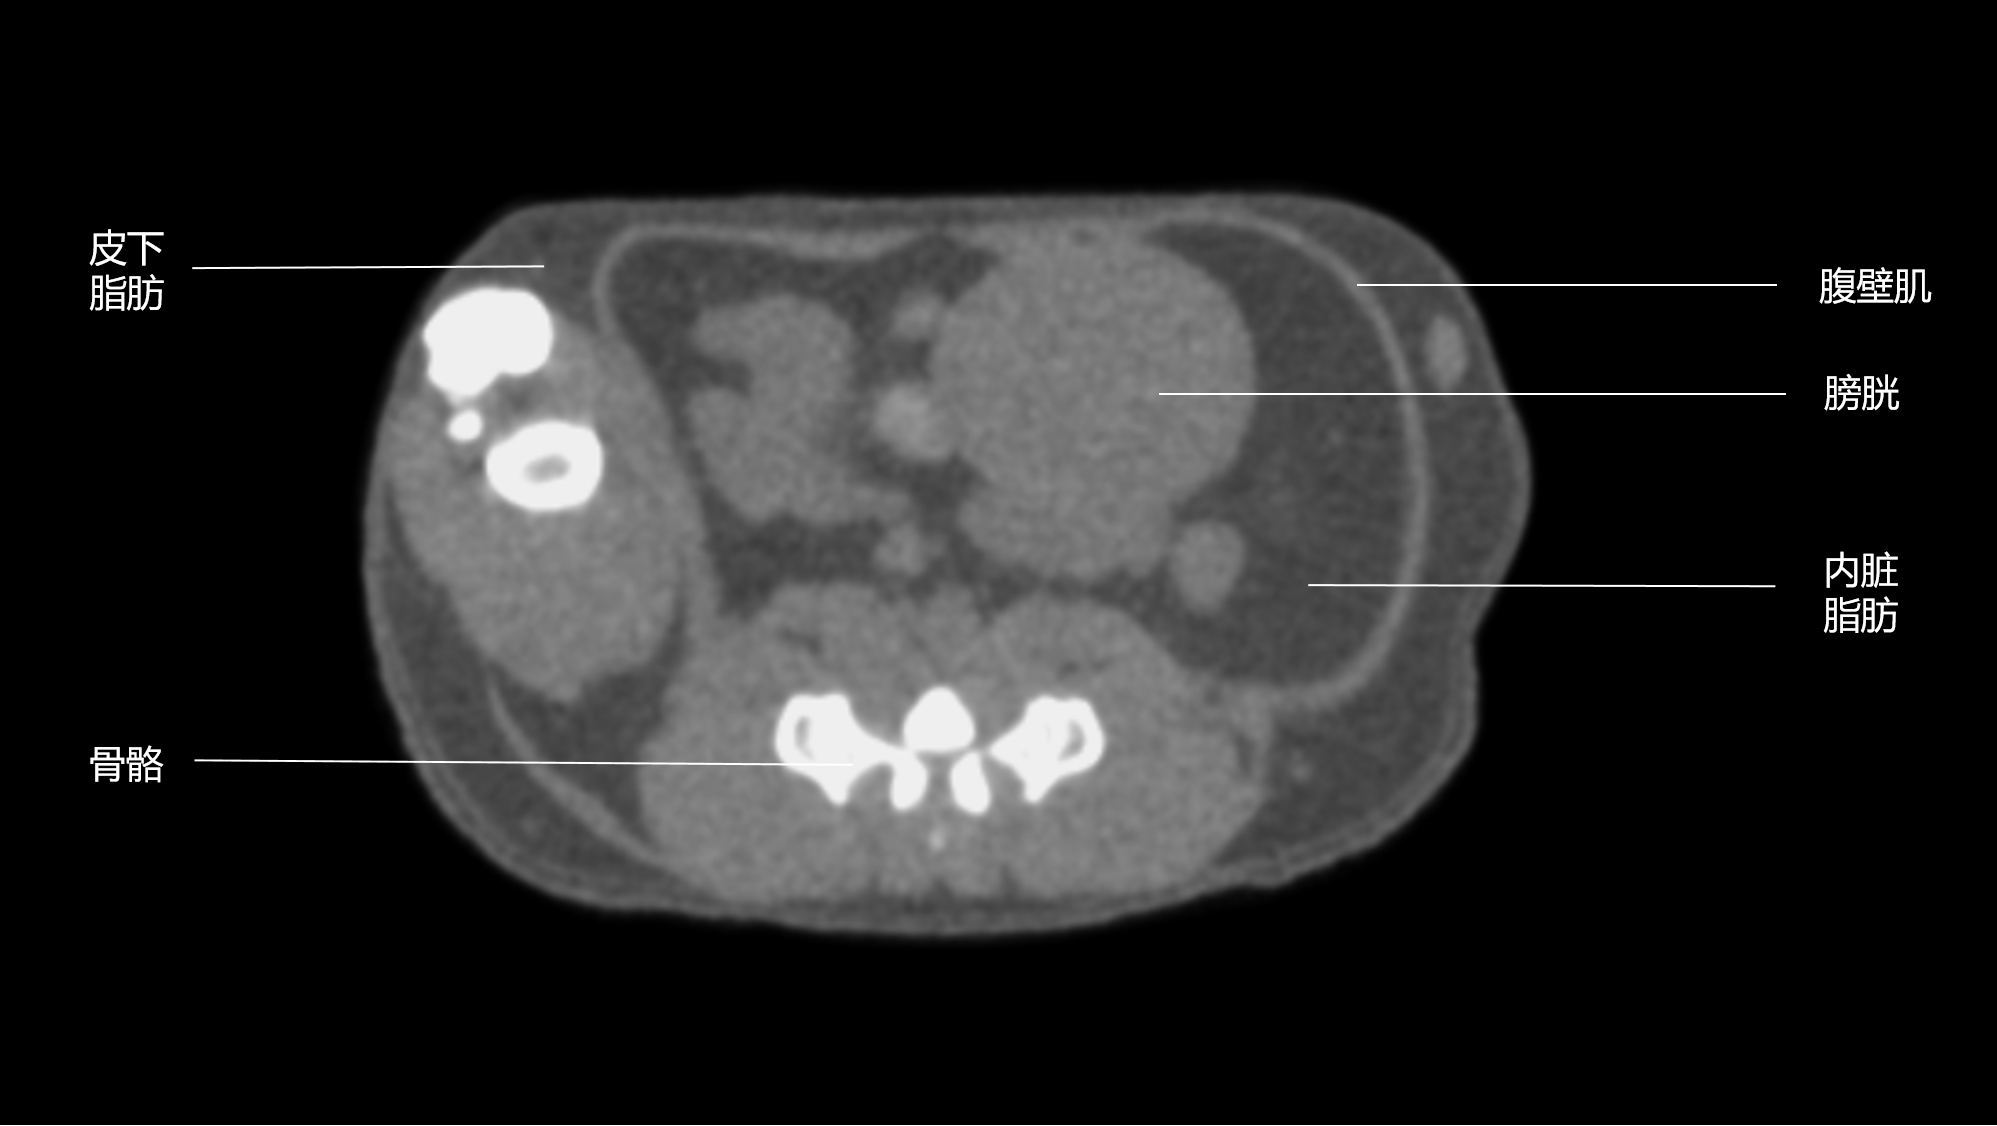

Micro-CT凭借其高分辨率、无创性等优势,成为精确定位和量化脂肪组织的理想工具。不同脂肪类型(如白色脂肪、棕色脂肪)对X射线的吸收特性存在差异:白色脂肪密度较低(-100至-30 HU),在CT图像中呈深灰色;而肌肉(30-50 HU)和骨骼(>400 HU)分别显示为浅灰色和白色。这种密度差异使得Micro-CT能够通过算法自动区分脂肪与其他组织,实现精准分类。

图二:A)小鼠腹部Micro-CT二维矢状面;B脂肪分割分离并分类,皮下脂肪显示为色,内脏脂肪显示为色。